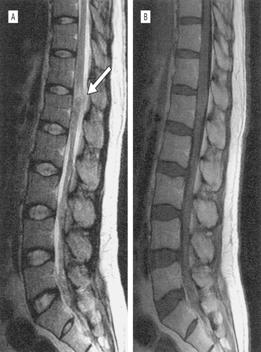

Xác định vị trí thương tổn bằng chụp cắt lớp vi tính (CT) hoặc chụp cộng hưởng từ (MRI) sẽ giúp cho chẩn đoán bệnh sán nhái tốt, nhất là thể sán não. Rạch và loại bỏ thương tổn và xác định loài sán để đưa ra chẩn đoán xác định. Trong trường hợp thể não, xét nghiệm ELISA dịch não tủy hoặc xét nghiệm huyết thanh sẽ giúp ích nhiều cho chẩn đoán, nhưng thường được khẳng định sau khi đã bắt được con sán. Chụp CT giúp hỗ trợ cho chẩn đoán lâm sàng, thường thương tổn có đặc điểm giảm âm, dãn não thất, các nốt bất thường, có nhiều vùng can xi hóa. Các chuyên gia khuyên nên chụp lại CT để đánh giá sự thay đổi kích thước cũng như vị trí tổn thương để chỉ định điều trị kịp thời nếu vẫn còn thương tổn.

Hình 25

CT và MRI đặc biệt hiệu quả trong chẩn đoán bệnh sán nhái ở não vì các hình ảnh thể hiện trong nhu mô não. Thông qua phân tích hồi cứu 25 ca sán trên não từ năm 2000-2006, tác giả Song và cộng sự tìm thấy một số đặc điểm có thể áp dụng như một khung chẩn đoán áp dụng trong tương lai mà không cần thực hiện sinh thiết hay phẩu tích mô thương tổn. Đặc điểm tìm thấy phổ biến nhất là dấu đường hầm ("tunnel sign") trên phim MRI cho thấy vết di chuyển của sán, trong khi đó hình ảnh thường thấy là hình tăng đavòng tròn hợp nhất, hay nhiều hình tràng hạt (thường là 3-6 vòng). Siêu âm tổng quát với nhiều loại đầu dò khác nhau cũng cho thấy có hữu ích trong chẩn đoán nhiễm trùng sán nhái trên các mô mềm và một số tạng.

Các nghiên cứu của Song còn đề nghị bổ sung với các dữ liệu về bệnh sử lâm sàng, xét nghiệm ELISA và hình ảnh của MRI hay CT scans đủ để chẩn đoán bệnh sán nhái. Tuy nhiên, các thương tổn này đôi khi dễ bị nhầm lẫn với thương tổn do lao. Trong một trường hợp sán nhái ở não không được chẩn đoán trong vòng 4 năm, khi chụp đã cho thấy chùm vòng tròn do chuyển từ bên phải sang bên trái của não, cuối cùng sán đã được tìm thấy qua sinh thiết.